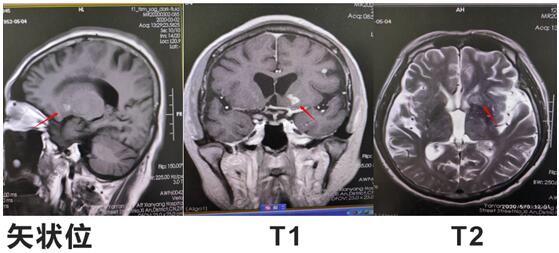

患者邱某,男,67歲 ,因“反復低熱頭痛40余天”入住我院神經內科三病區(qū),入院后行神經系統(tǒng)體格檢查示:表情淡漠,腦膜刺激征陽性;行顱腦磁共振增強掃描示:顱內可見多發(fā)點狀及小片狀結節(jié)灶,增強掃描呈小片狀及環(huán)形明顯強化,考慮①感染性病變,結核性腦膜炎可能,②轉移瘤待排:請結合臨床實驗室檢查;行腰椎穿刺術示:顱內壓310mmH2O,潘氏試驗陽性,并于腦脊液中檢測出結核分枝桿菌(咸陽市首例)。腦脊液常規(guī):淡黃色清亮,白細胞計數(shù) 210*106/L,潘氏試驗陽性,中性粒細胞比率 90.0%。腦脊液生化:葡萄糖 1.40mmoI/L,氯 105.5mmol/L,微量總蛋白 2749mg/L,陳萍主任醫(yī)師、代昌飛副主任醫(yī)師及科室其他醫(yī)師慎重討論后考慮:結核性腦膜炎,并立即制定抗結核、降低顱內壓、抑制腦水腫、減輕炎癥反應等相關治療方案。王寶艷護士長指導護理應加強護理,早期康復。經討論匯總,為該患者制定特色治療方案,動態(tài)調整,密切觀察。在科室醫(yī)生護士的精誠協(xié)作下,患者渡過險關。復查腰椎穿刺術:初壓:170mmH20,常規(guī):潘氏試驗陽性;白細胞計數(shù) 120*106/L。淋巴細胞百分率 10.0%,中性粒細胞百分率 90.0%。生化:微量總蛋白 1503mg/L。出院后繼續(xù)抗結核治療。